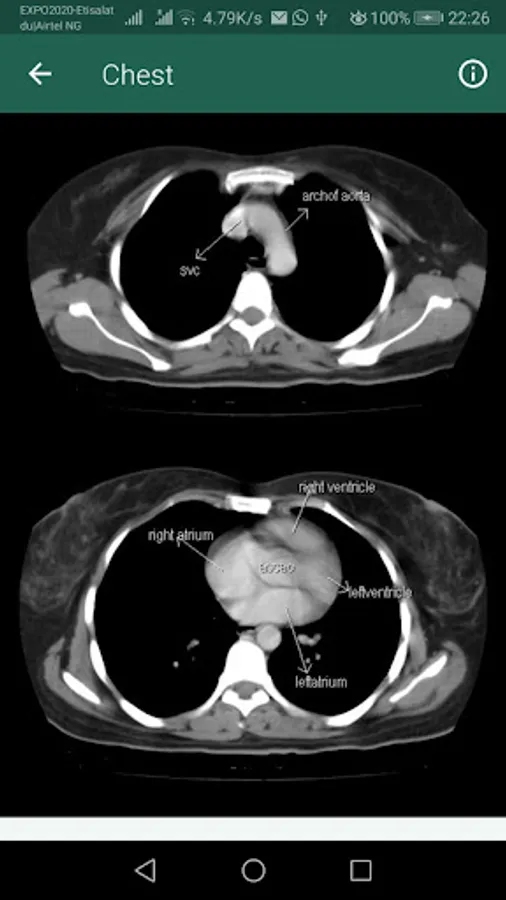

An ideal resource for the classroom or clinical setting, Sectional Anatomy for Imaging Professionals, the App provides a comprehensive, and highly visual approach to the sectional anatomy of the entire body. Side-by-side presentations of actual diagnostic images from both MRI and CT modalities and corresponding anatomic line drawings illustrate the planes of anatomy most commonly demonstrated by diagnostic imaging. Easy-to-follow descriptions detail the location and function of the anatomy, while clearly labeled images help you confidently identify anatomic structures during clinical examinations. In all, it’s the one reference you need to consistently produce the best possible diagnostic images.

Side-by-side presentation of anatomy illustrations and corresponding CT and MRI images clarifies the location and structure of sectional anatomy.

Reference drawings and corresponding scanning planes appear on appropriate pages with the actual images, so they are easily referenced for correlation between the scanning planes and the resulting images.